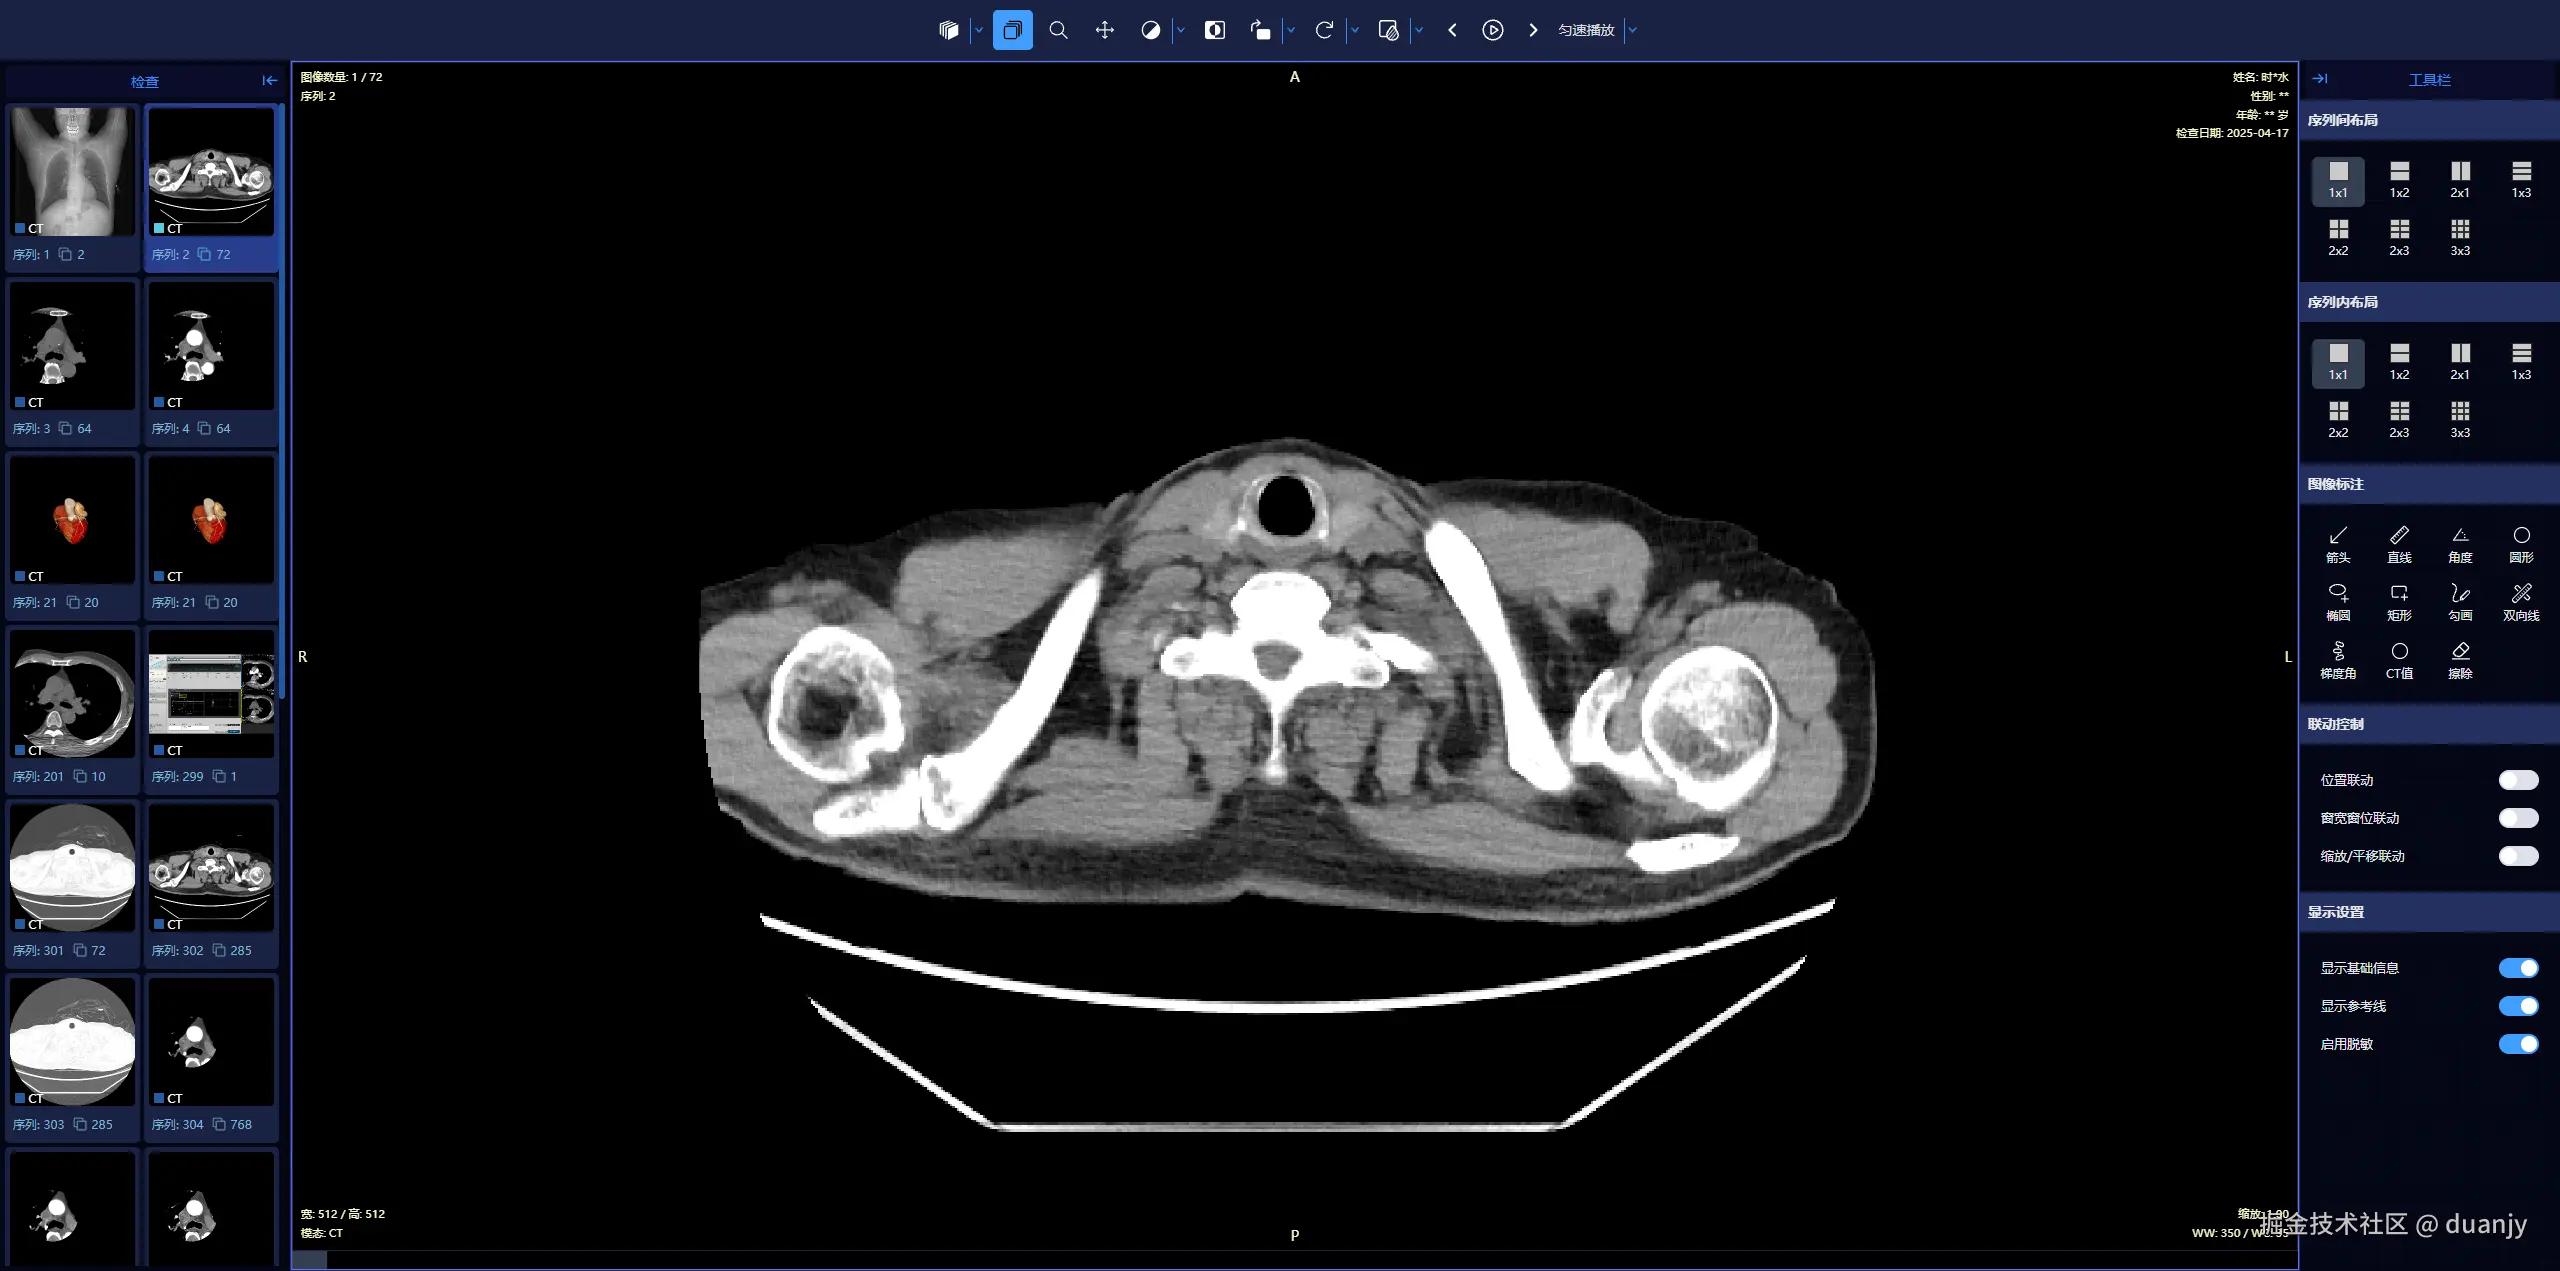

1. 手机端 – 二维平片

mobile.png

支持在 PC 和手机端 打开,可以查看 二维平片三维重建